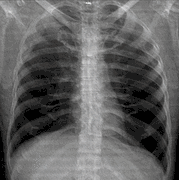

A chest radiograph, called a chest X-ray (CXR), or chest film, is a projection radiograph of the chest used to diagnose conditions affecting the chest, its contents, and nearby structures. Chest radiographs are the most common film taken in medicine.

![]() A normal posteroanterior (PA) chest radiograph of someone with Interstitial Pneumonia. Dx and Sin stand for "right" and "left" respectively. | |